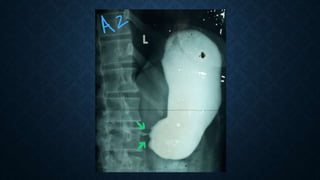

This document provides an overview of x-rays for medical students, covering topics such as ensuring x-rays are well-aligned, exposure levels, common artifacts and anatomical features, abdominal x-ray positions and views, and specialized x-rays including barium swallows, enemas, and tests to examine the esophagus, small bowel, biliary tree, and kidneys.